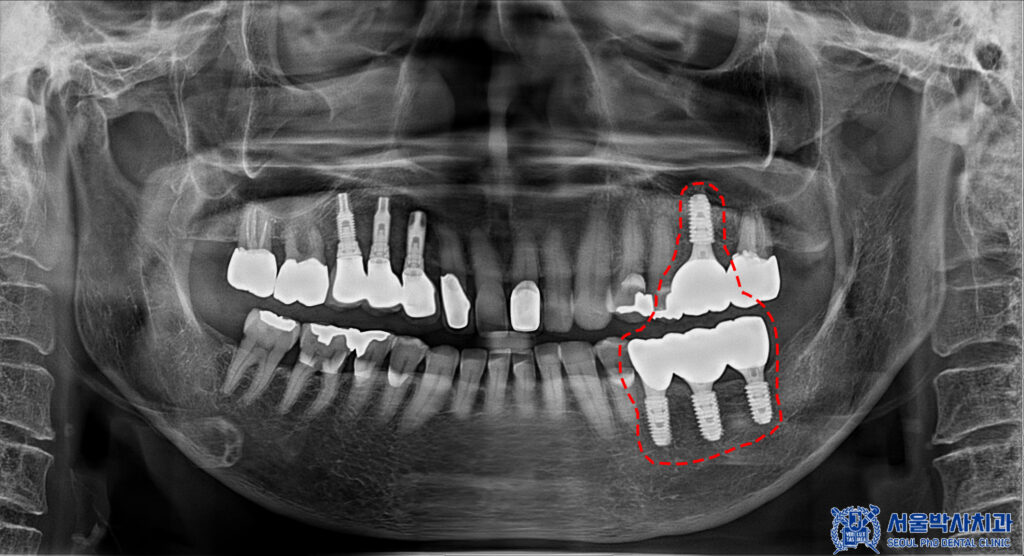

환자분께서는 왼쪽 아래 어금니가

소실된 상태였으며,

왼쪽 위 치아의 보철물 하방으로

충치가 보였습니다.

이러한 경우,

충치 치아 발치 후 상실된 부분을 포함해서

임플란트를 식립 하면 되지만

현재 환자분께서는 골다공증 주사제를

맞고 계신 상태셨습니다.

그래서 먼저 왼쪽 아래 상실된 부분의

무절개임플란트 3개를 식립 하기로

계획을 수립하였습니다.

아래쪽의 보철이 마무리된 후,

발치했던 부분의

뼈이식을 포함한 무절개임플란트를

식립 하였습니다.

이때, 골다공증 주사제 시기 또한

본원에서 체크 및 조정하여

안정적으로 수술을 진행하였습니다.